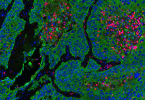

Erster hochauflösender Einzelzell-Atlas zum Lungenkarzinom